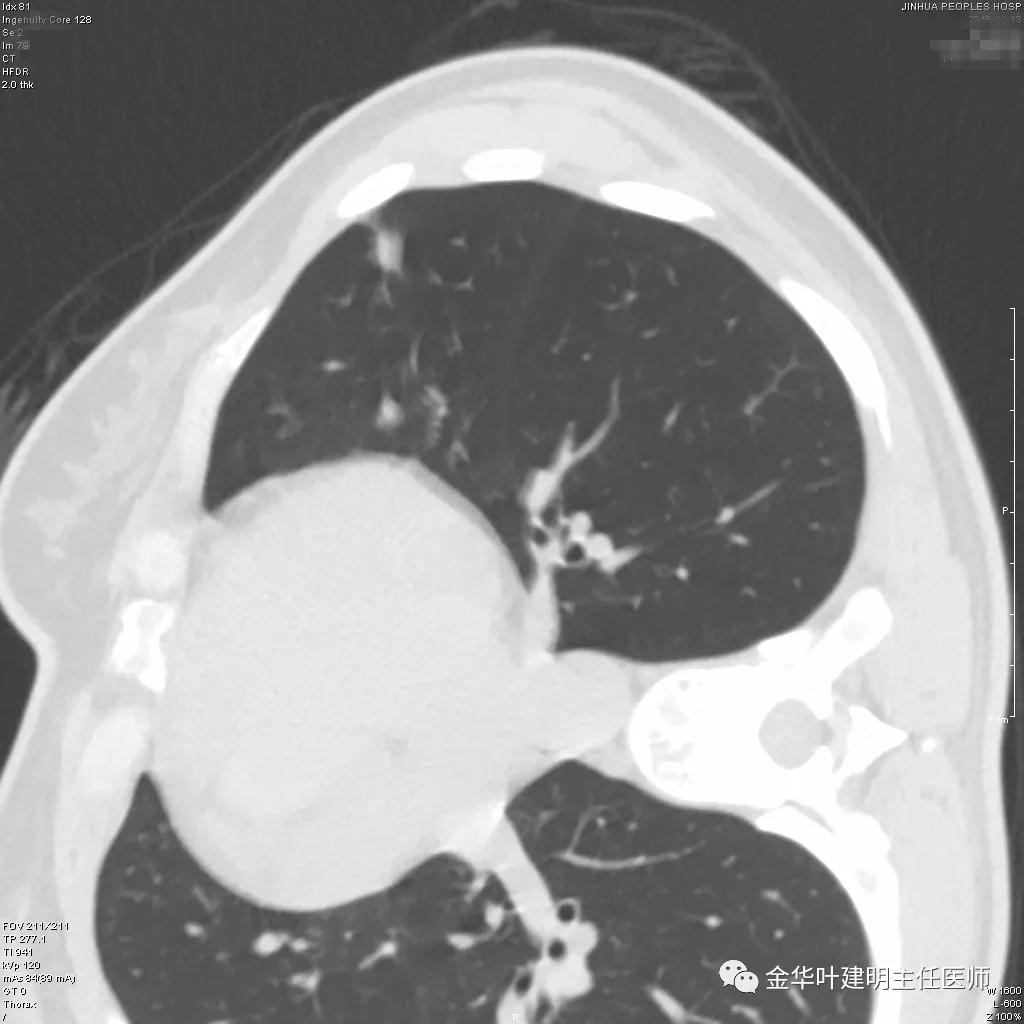

病灶实性,但收缩力弱,绿色箭头示病灶边缘有一圈晕征(模糊且均匀)

病灶实性,但收缩力弱,没有细毛刺征,实性部分比较圆润,绿色箭头示病灶边缘有一圈晕征(模糊且均匀)

此层面红色箭头示有卫星灶,粉色箭头示主病灶

红色示卫星灶,粉色示病灶,绿色示边缘晕征

此层面相对最不舒服,病灶表面不平整。桔色箭头示血管进入病灶,但仍有绿色箭头示病灶有晕征(边缘是模糊的,不似肿瘤那种细毛刺且相对清楚轮廓)

紫色箭头示病灶的边缘向内凹陷,说明无膨胀性,绿色示晕征,粉色箭头指向病灶

此层面示病灶呈三角形,缺乏膨胀性,边缘较直,没有毛刺征,实性部分没有收缩纠集感,绿色箭头示晕征